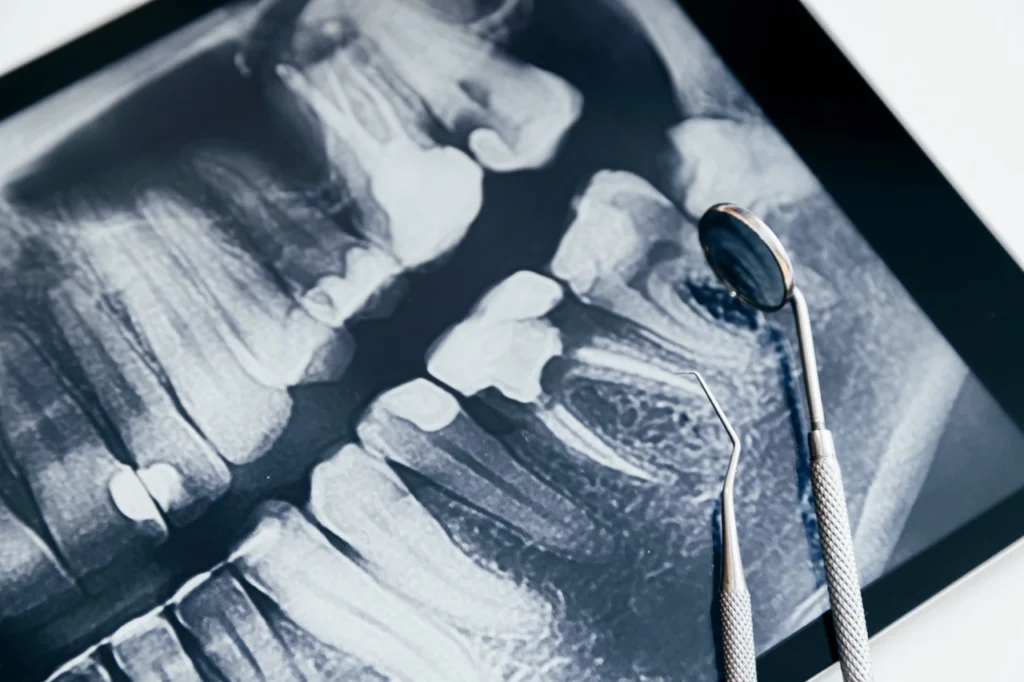

初診時會先拍攝⼝腔 X 光,了解智⿒位置、⾓度與是否貼近神經。森美學牙醫會為您拍攝全⼝X光, 精準判斷智⿒位置與拔除風險。